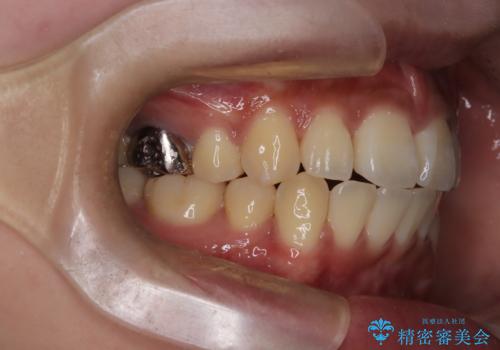

- 前歯の突出が強く、口元が前に出ている印象を改善するため、上下左右の第一小臼歯(4番)を抜歯する矯正治療を計画しました。抜歯により得られたスペースを利用して、前歯を後方へと移動させて整列します。治療には目立ちにくい透明な審美ブラケットとワイヤーを使用し、毎月1回の調整を行いながら徐々に歯を動かし、約2年で口元全体を整える計画としました。

前歯が前に出ているため口元が突出し、唇が閉じにくいなどの悩みを抱えておられました。治療にあたり上下左右の第一小臼歯を抜歯し、十分なスペースを作ることで前歯を効果的に後方へ移動させました。装置には透明で目立ちにくい審美ブラケットを採用し、治療中の審美的ストレスを軽減しました。定期的な調整を通じて無理なく確実に歯列を整え、前歯の突出感を解消。治療後は口元の印象が自然で美しく改善され、患者様には非常にご満足いただけました。